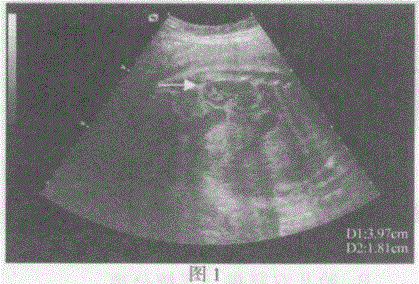

问题 临床资料:女,33岁,孕35周,常规超声检查。 超声综合描述:图1、图2箭头所指是胎儿哪一部位: 超声提示:

选项 A.胎儿肠管 B.胎儿脊柱 C.胎儿肾脏 D.胎儿心脏

答案 C